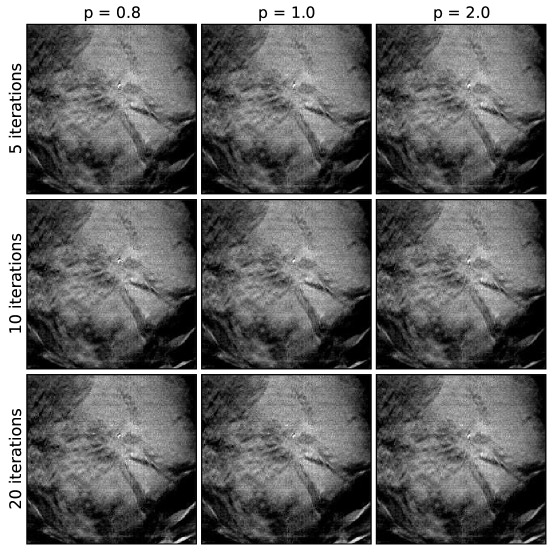

V.5 Case 2: uniform mass

For the next case, there is a uniform mass, as can be seen in the EM image-reconstructions in Fig. 9. As was done in the previous case, we present a spread of images in Figs. 10, 11, and 12 from the ASD-POCS algorithm for the same sets of algorithm parameters, covering a range of - and -values. The iteration number dependence appears to be weak for ASD-POCS. The conspicuity of the mass for this case does not vary with algorithm parameters nearly as much as the microcalcification conspicuity of the previous case. There are many reasons for this. First, the X-ray attenuation coefficient of the mass is less than that of calcium, so the contrast that can be potentially regained is not as great. Second, the lower reconstructions tend to yield sharper edges, but this does not have as large an effect on the mass which is substantially bigger than microcalcifications. Finally, as pointed out earlier, mass conspicuity tends to depend on background structure noise. As this type of background is physically there, low image-reconstruction sharpens the edges of the background features just as much as the mass’s edges. Thus, the conspicuity of the mass may not improve dramatically as is lowered. In any case, there are subtle differences between the images, and these differences may have an impact on human or machine observers.

Comparing the visual quality of the images of the present case with the previous one, it is interesting that similar -values do not yield similar apparent image quality. For example, for the present case appears to be quite noisy, even taking into account differing gray level windows, relative to for the previous case. For the 3 sets of -values, appears to yield, visually, the best images for this mass case, while seems to best for the previous, microcalcification case. These, differences are likely due to varying quality of the acquired projection data. A quantitative discussion of algorithm performance across different DBT cases will be further elaborated on in Sec. V.7.